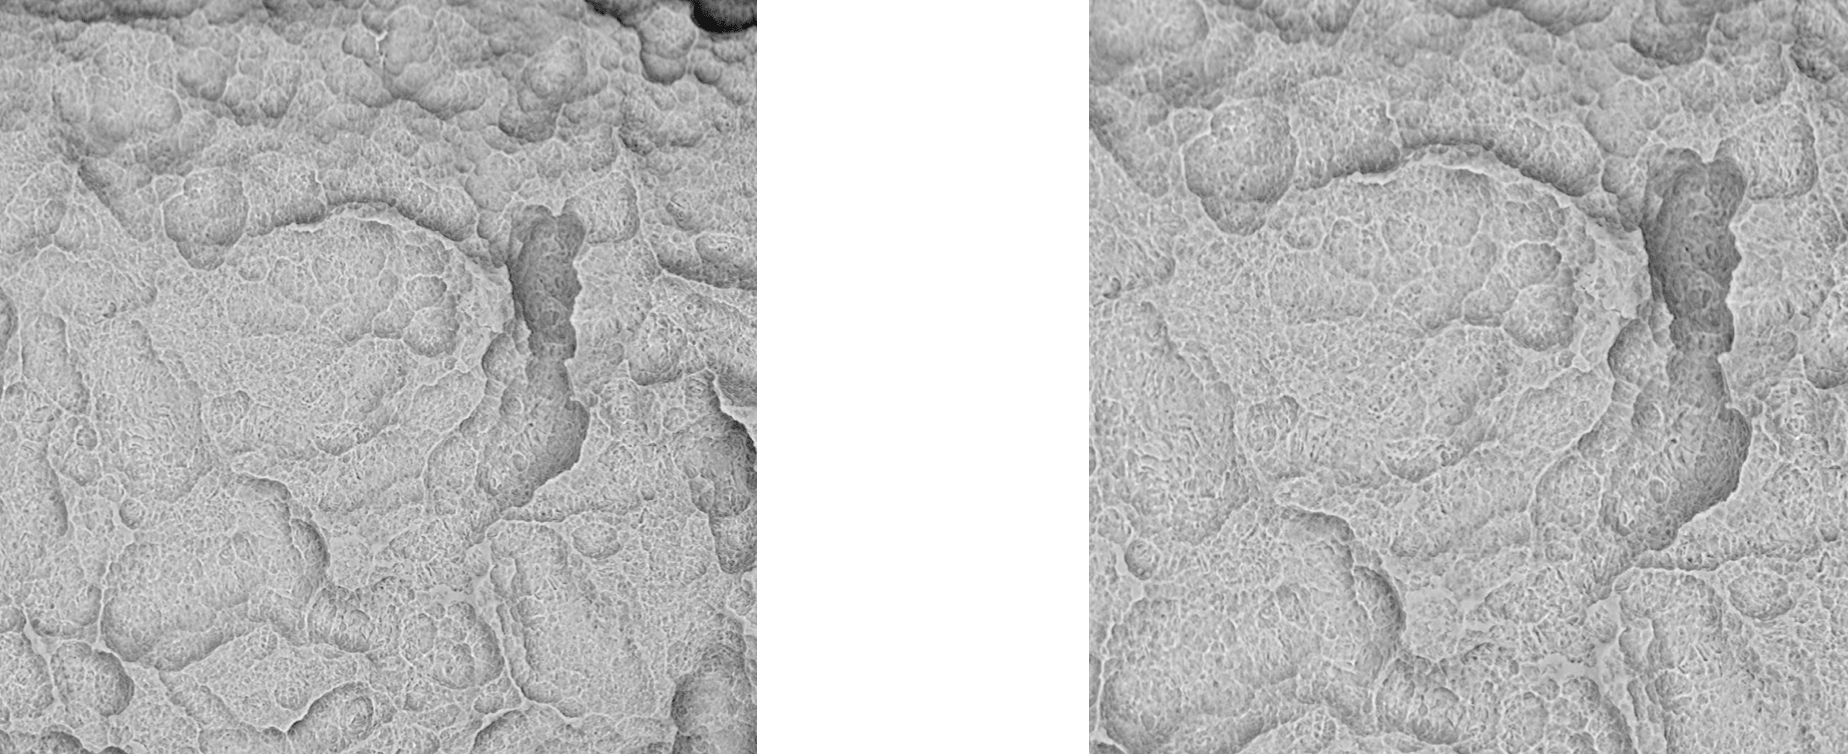

3.3 Surface-Topography - Material Contrast Images (Body)

Surface-Topography - Material Contrast Images (Body)

The implant “SPI Spiral Implant” provided by Alpha-Bio Tec for this analysis showed no significant traces of inorganic or organic residues and high mechanical precision.